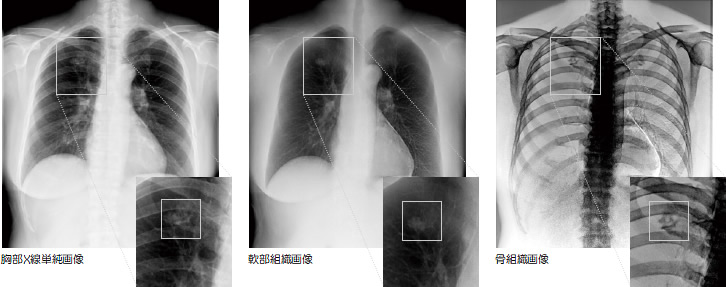

2016年12月に、胸部X線撮影装置を競艇の交付金による2016年度日本財団の助成金を受けて、GEヘルスケアジャパン社製Discovery XR656 Plusに更新しました。

この装置には、2種類の異なる管電圧で撮影した2枚の撮影データからエネルギー差による情報を差し引くことで、通常の単純エックス線画像に加え、骨を除いた軟部組織画像と骨組織画像を作成できるデュアルエナジーサブトラクションという機能が搭載されています。

この機能を利用することにより、低線量でより高画質な胸部X線写真を提供できるようになりました。

胸部X線撮影装置(GEヘルスケアジャパン社製Discovery XR656 Plus)